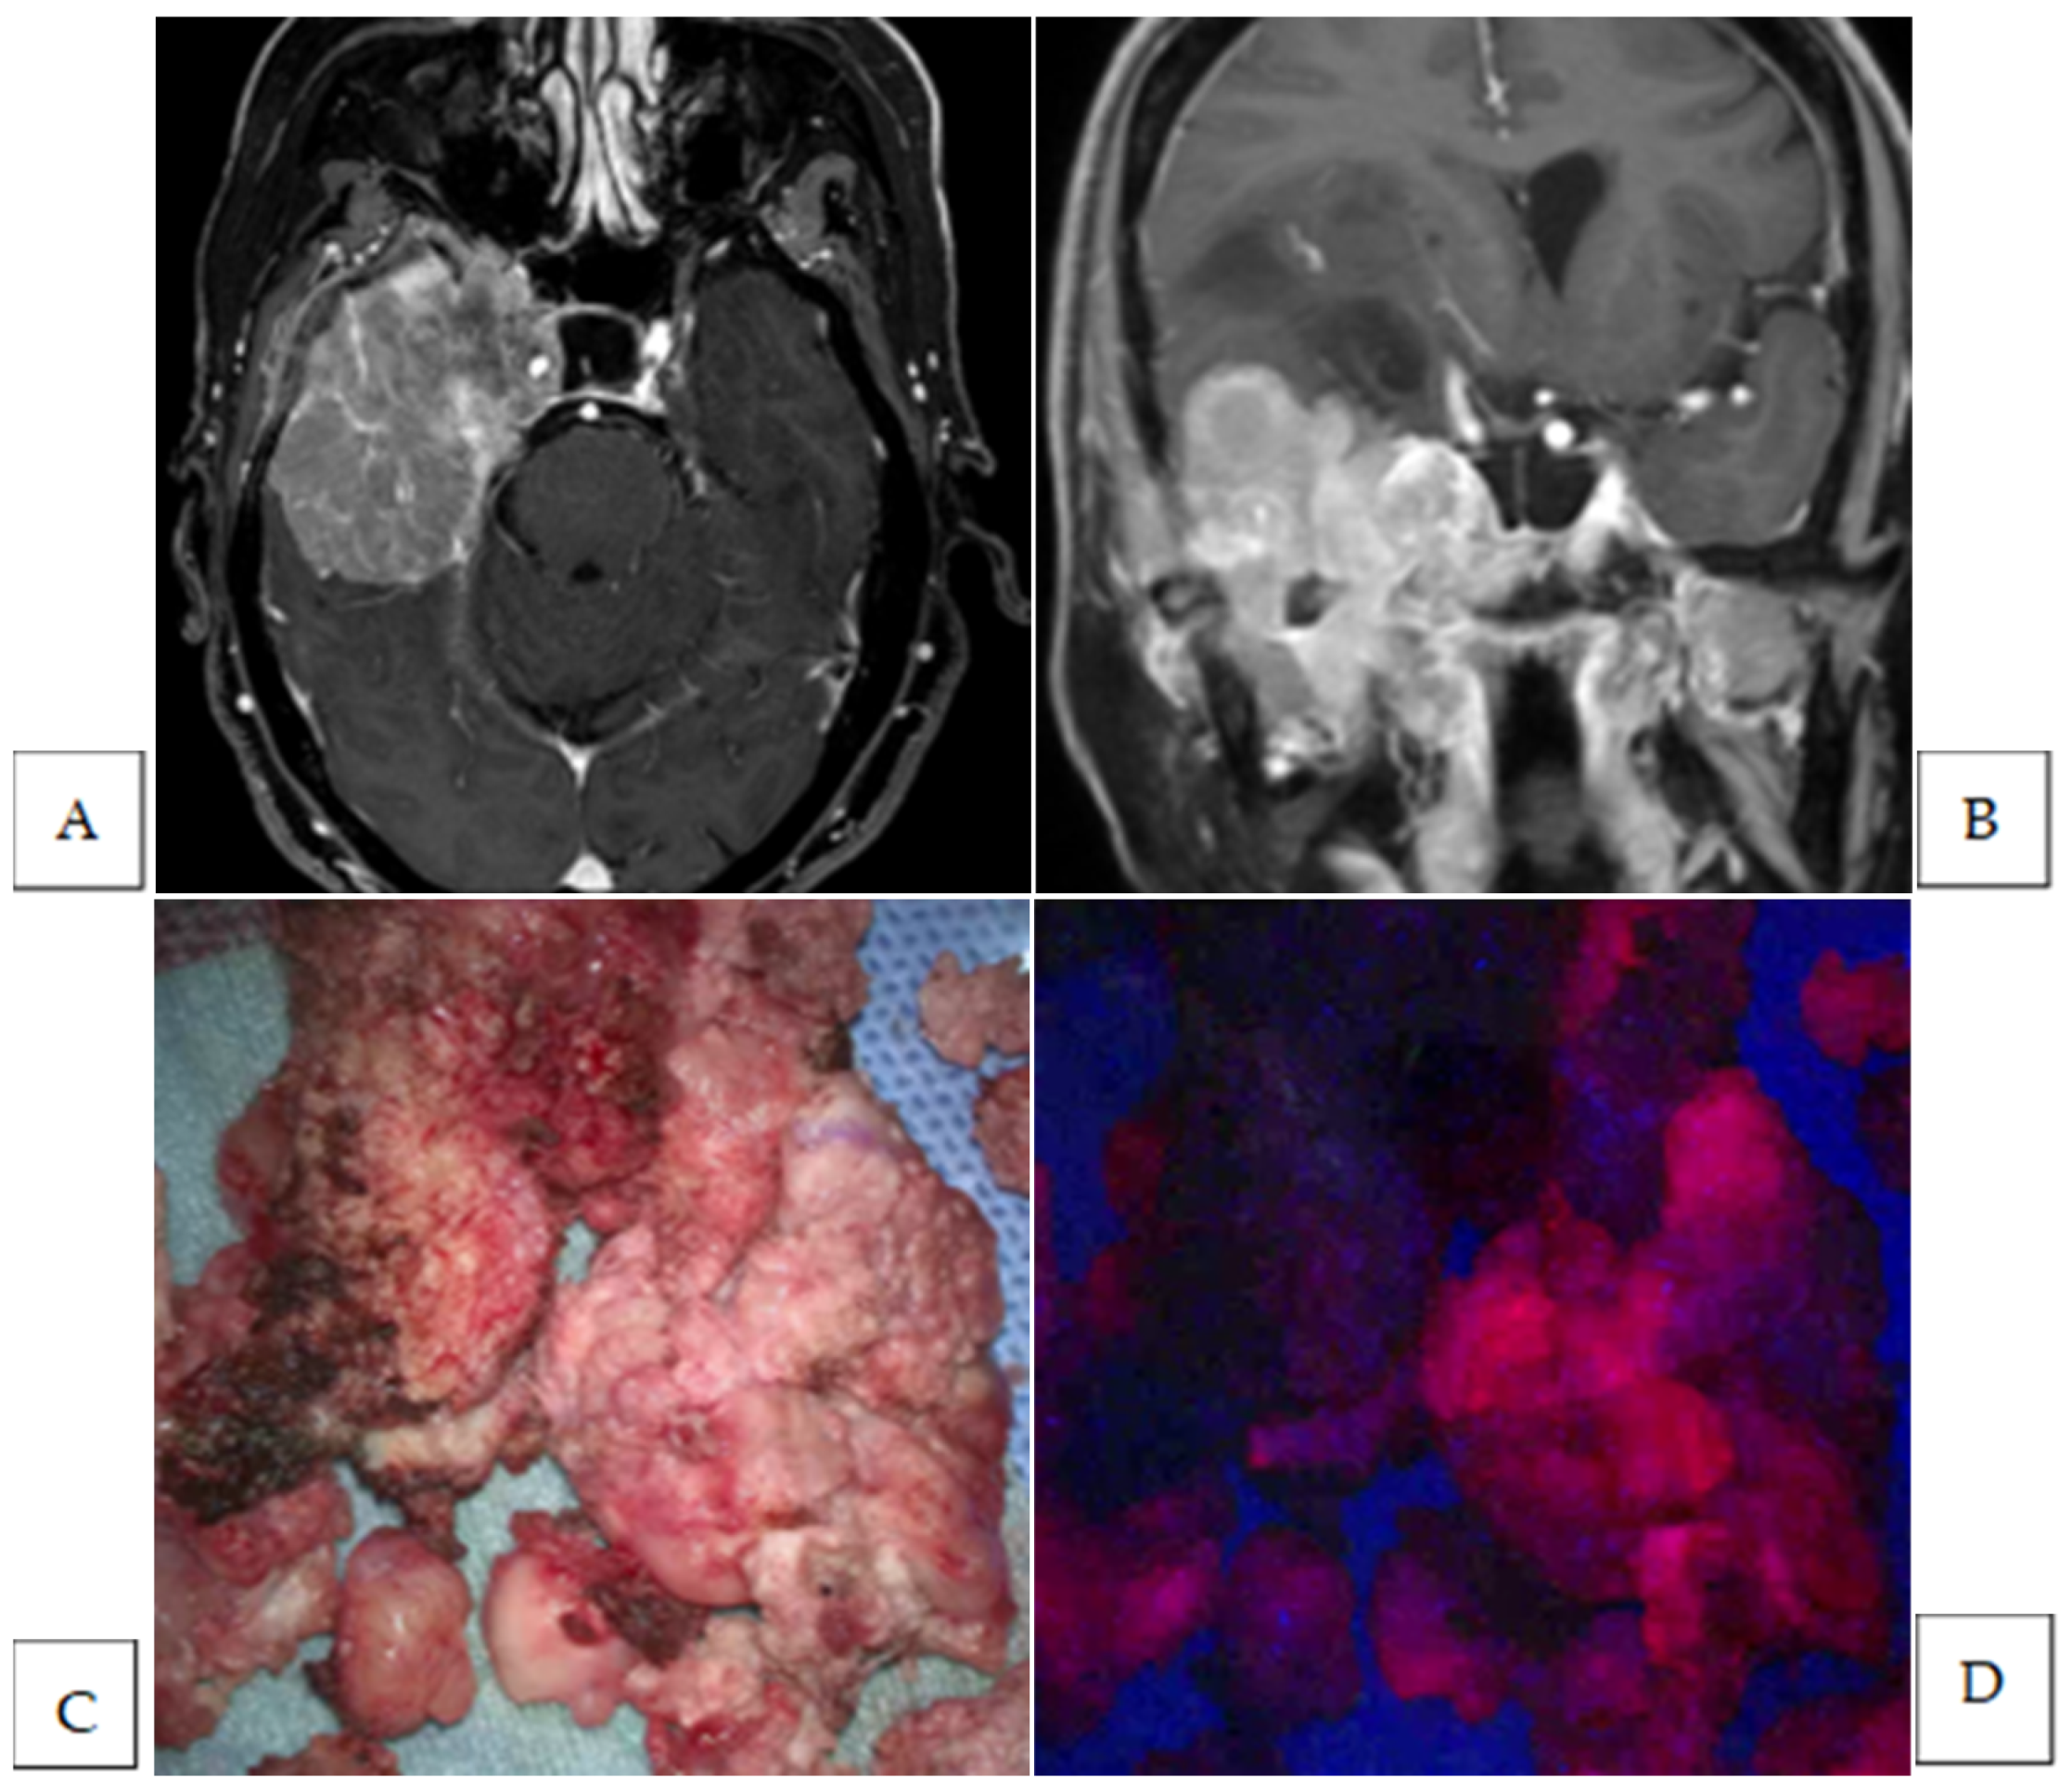

3. Results